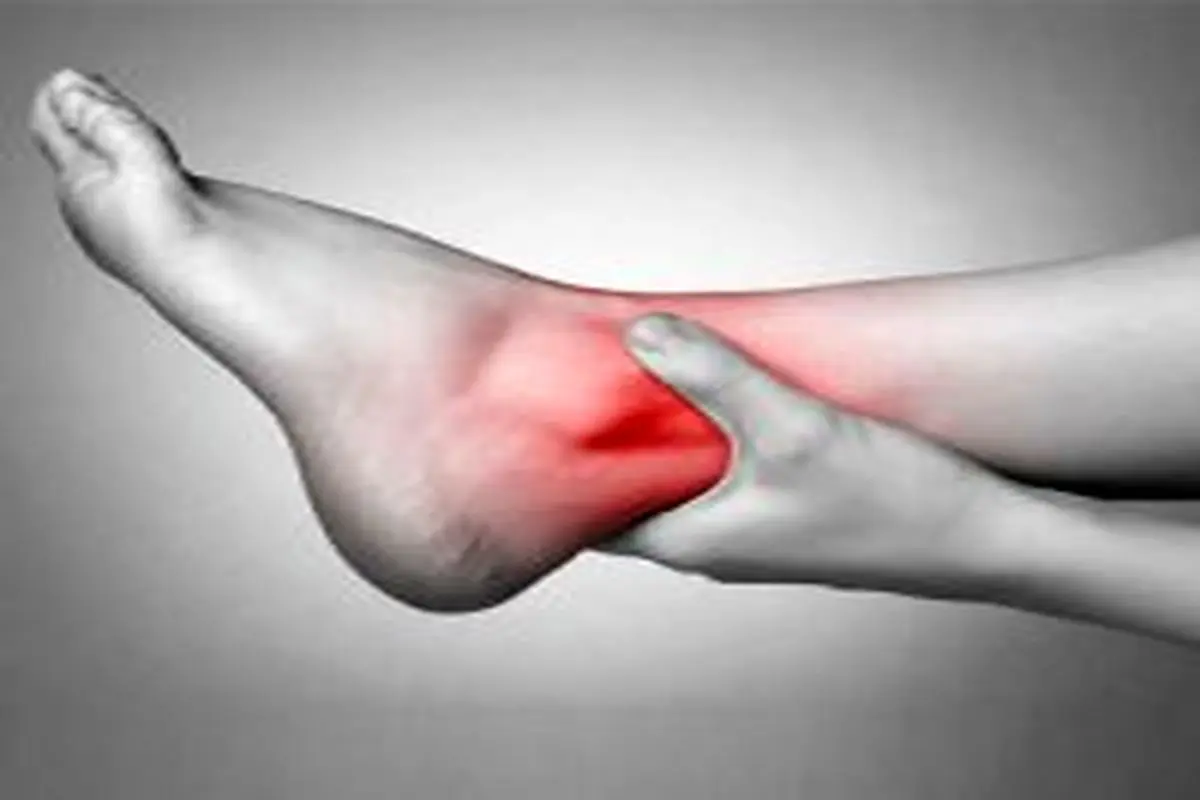

انجام حرکات پا

بسیاری از ما در طول روز، بیشتر وقتمان را در حالت نشسته سپری میکنیم که باعث کاهش جریان خون در پاها میشود. اگر نمیتوانید گزینه راه رفتن را انتخاب کنید، میتوانید هرازگاهی در حین کار برای تقویت گردش خون در محدوده پا حرکاتی مانند چرخش مچ پا، خم و راست کردن پا و حرکت دادن انگشتان را انجام بدهید.

بالا نگه داشتن پاها

مقابل دیوار به پشت دراز بکشید و پاها را به طور عمودی به دیوار تکیه دهید. بعد از گذراندن یک روز به طور نشسته یا ایستاده، فقط چند سانتیمتر بالاتر قرارگرفتن پاها نسبت به سر و قلب، یک راه عالی برای به جریان افتادن خون در سراسر بدن به جای

گیر افتادن آن در پاهاست.

خودداری از انداختن پا روی پا

کسانی که بیشتر در معرض ایجاد لخته قرار دارند، بهتر است از انداختن پا روی پا خودداری کنند. به گفته کارشناسان، نشستن به این حالت، فشار را در رگهایی که مسؤولیت برگشت دادن خون به قلب را دارند، افزایش میدهد. فشار پایی که روی پای دیگر است، مانع جریان خونرسانی عادی در پای زیرین میشود و میتواند به تضعیف یا آسیب رگهای پا منجر شود. این شرایط باعث میشود خون در درون رگ، لخته شود.